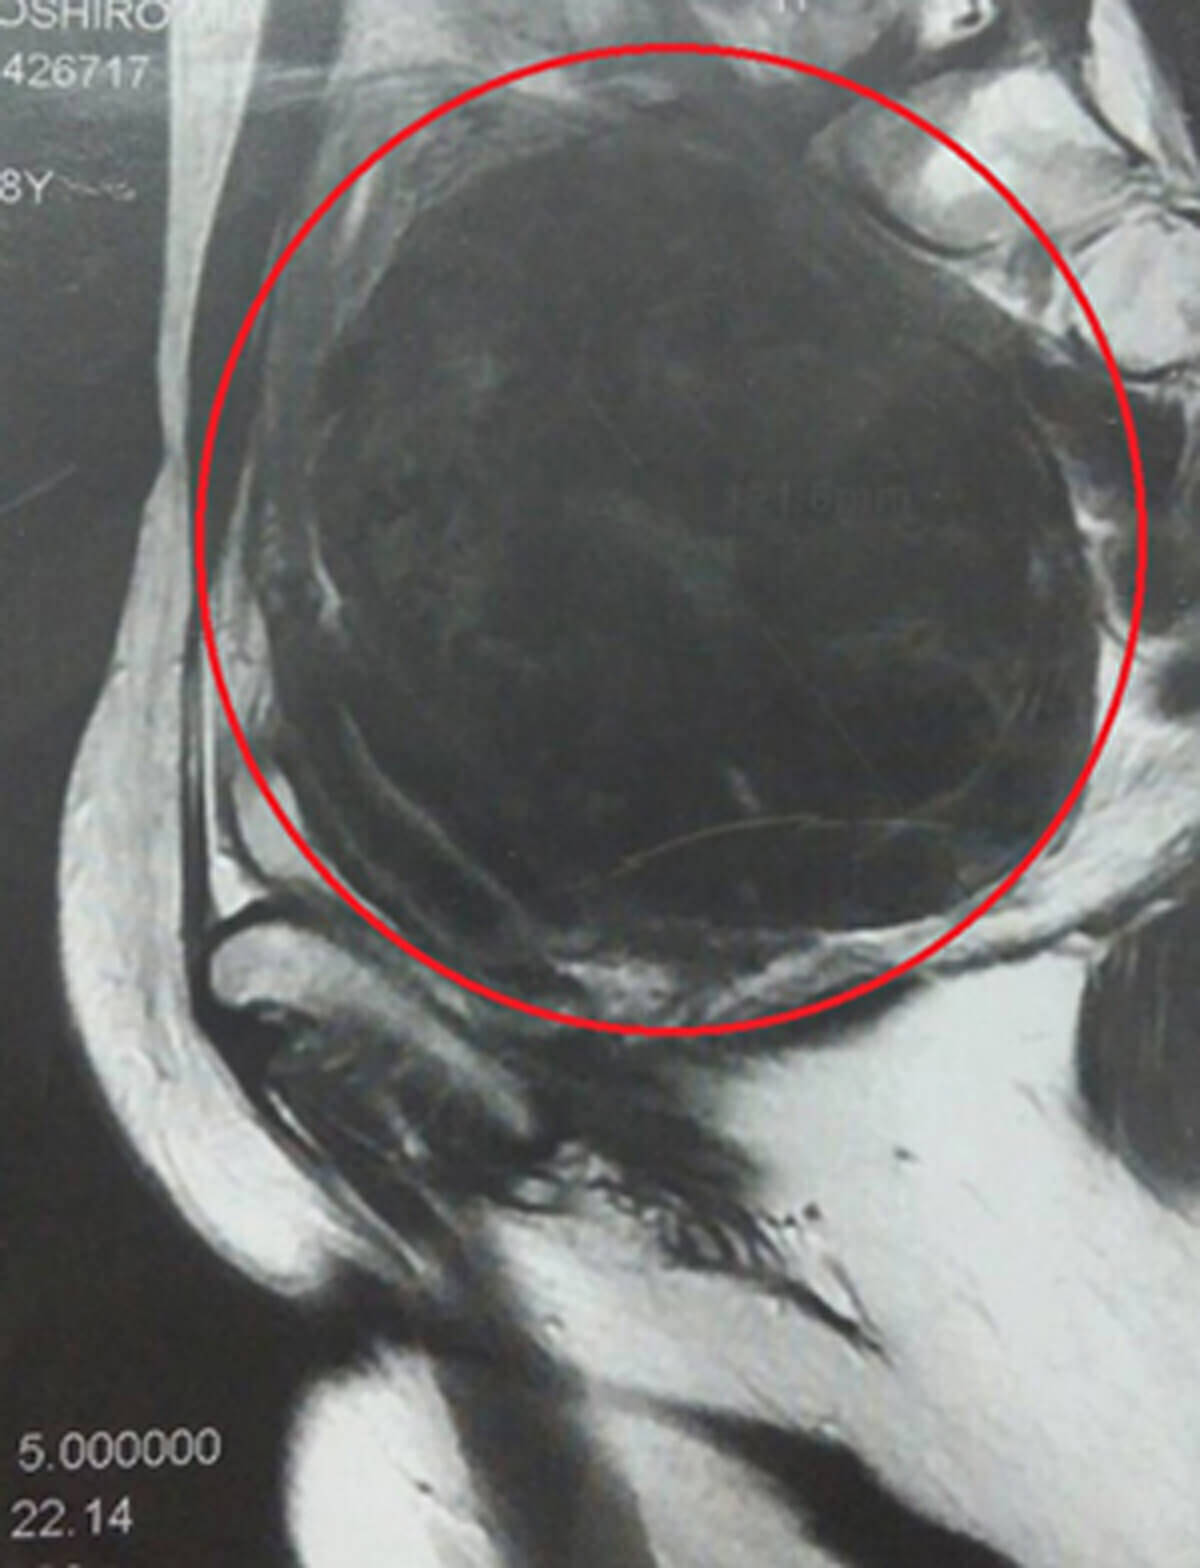

子宮筋腫の大きさ 何センチになったら手術 子宮筋腫

子宮筋腫の大きさは何センチ 放置するとどうなる

子宮がん検診で しこり 12センチ発覚 38歳で 子宮筋腫 手術を決意したワケ 2019年3月22日 エキサイトニュース